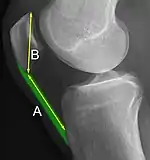

The Insall-Salvati ratio helps to indicate patella baja on lateral X-rays, and is calculated as the patellar tendon length divided by the patellar bone length. An Insall-Salvati ratio of < 0.8 indicates patella baja.[6]